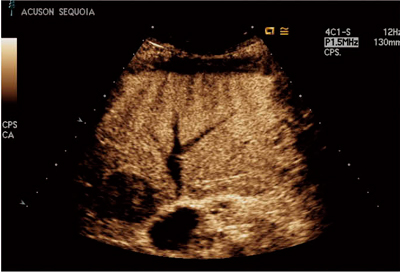

図2 CPSによる造影エコーの例

肝細胞がん,後期相。肝全域にわたり均一な染影効果が得られている。深部のwashoutも明瞭に表示。

(画像ご提供:兵庫医科大学・飯島尋子先生)